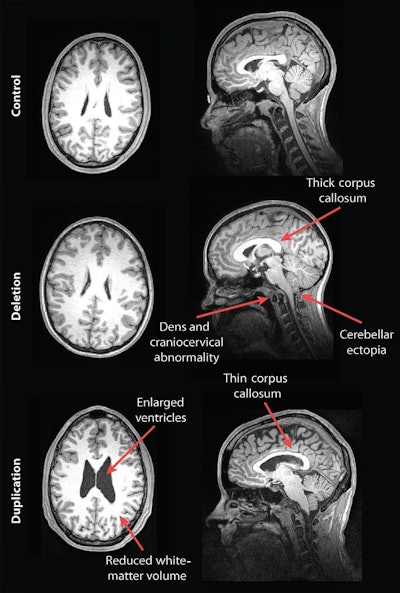

Their analysis showed some striking differences in the brain structures of carriers of deleted and duplicated chromosomes compared with noncarriers. For example, the corpus callosum was abnormally shaped and 16% thicker in the deletion carriers but 19% thinner in the duplication carriers, compared with the control group and family noncarriers.

MR images of a control subject, deletion carrier, and duplication carrier. The deletion carrier's sagittal image shows a thick corpus callosum, dens and craniocervical abnormality, and cerebellar ectopia (arrows). The sagittal image for the duplication carrier shows the thin corpus callosum (arrow), while the axial image (left) displays increased ventricle size and decreased white-matter volume. Images courtesy of Radiology.

In addition, compared with unaffected family noncarriers and control participants, carriers with the deletion at 16p11.2 also exhibited signs of overgrowth in the posterior fossa, with a 31% likelihood of an abnormal downward displacement of the cerebellum, also known as cerebellar tonsillar ectopia (30.7%) and 9% greater occurrence of structural defects in the base of the skull and cerebellum.

Compared with unaffected family noncarriers and controls, carriers with the duplication at 16p11.2 showed signs of brain undergrowth, such as 23% decreased white-matter volume and 24% more ventricular volume.